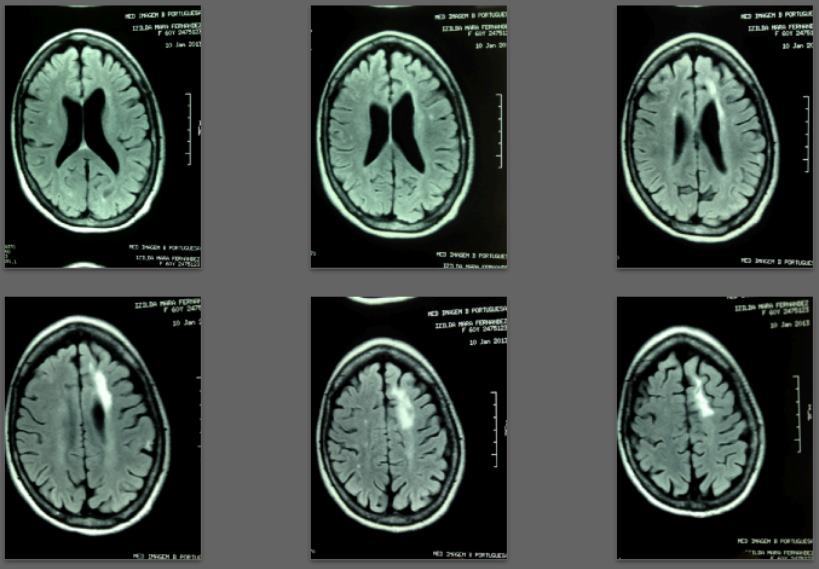

Before/after MRI images for one of 1,000+ patients of Dr. Coimbra

2008 Convulsive seizures Diagnosis: Balo’s concentric hemiparesis

Starting daily dose 25,000 IU; increased in stages to 80,000 IU on October 28, 2010. Asymptomatic since 2010.

2013 MRI